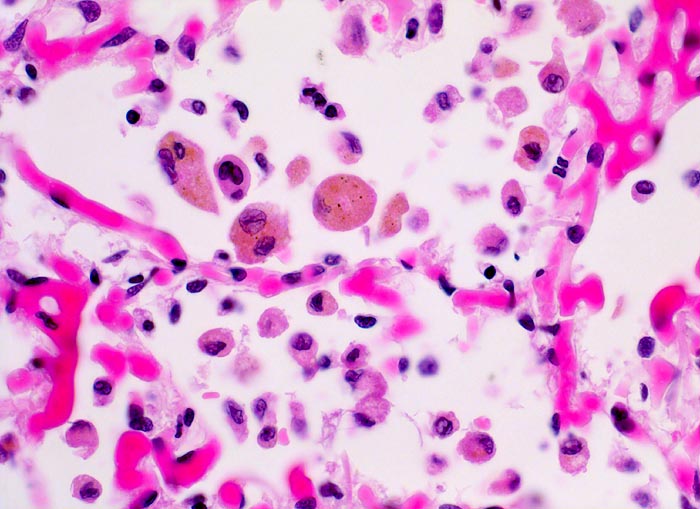

In einer frühen Phase kommt es zur roten Stauungsinduration, welche in eine braune Stauungsinduration übergeht. Die Eindrückbarkeit der Lungen ist aufgrund der Fibrosierung der Alveolarsepten vermindert. Die meist fleckförmige braune Verfärbung beruht auf der Anhäufung von hämosiderinhaltigen Herzfehlerzellen in den Alveolarlichtungen. Makrophagen in den Alveolarlichtungen phagozytieren die ausgetretenen Erythrozyten. Der Nachweis von Erythrozyten im Zytoplasma von Makrophagen spricht für eine frische Blutung. Nach 3-5 Tagen ist in den Makrophagen Hämosiderin nachweisbar. Das Hämosiderin lässt sich mittels Eisenfärbung (Berliner-Blau) zuverlässig von Staubpigment abgrenzen. Als sicheres Zeichen für eine ältere Blutung gelten >20% hämosiderinspeichernde Makrophagen in der bronchoalveolären Lavage (BAL). Die hämosiderinhaltigen Alveolarmakrophagen werden auch Herzfehlerzellen genannt, da sie gehäuft im Rahmen einer linkskardialen Stauung bei Mitralklappenstenose auftreten.

• Siderinhaltige Alveolarmakrophagen (=Herzfehlerzellen).

Morphologische Merkmale:

• Mediahypertrophie der Pulmonalvenen.

• Fibrosierung und Verdickung der Alveolarsepten.